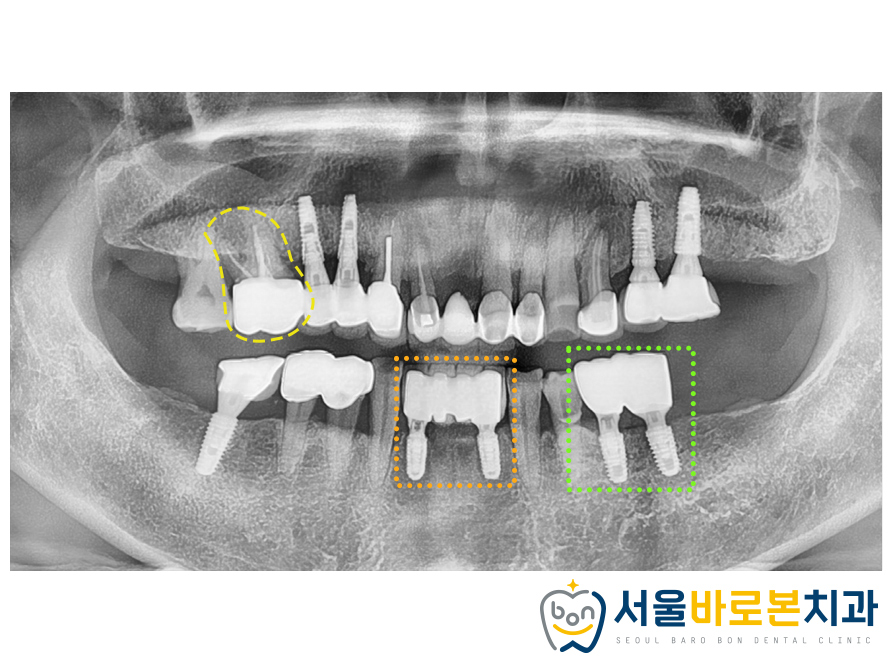

그리고 한달의 시간이 흐르고

식립하였던 임플란트

체크를 해보았는데요.

다행히 잇몸뼈에

임플란트 픽스처가

잘 고정이 되어있었습니다. 😊

이렇게 임플란트 수술 후

정기 체크를 통해

고정이 잘 된 것을 확인한 후

보철과정을 진행하게 됩니다.

픽스처가 뼈에 잘 유착된 것을 확인 한 후

본뜨기 작업을 진행해주었습니다.

본뜨기 작업을 위한 기구를 연결한 후,

올바르게 체결되었는지

확인하기 위해 엑스레이 사진을

촬영해 본 모습입니다.

크라운(보철물)을 만들어와

최종 보철물까지

모두 끼워드린 모습입니다.^^

총 2개월 반~3개월만에 완성해드렸습니다. 👍

자연치는 살려 쓰실 수 있도록 크라운 치료를,

파절된 부위와 흔들리는 부위엔

발치 후 임플란트를

성공적으로 마무리 해드렸답니다. 👍